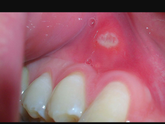

Девочки! Зайдите кто знаком с этим. Десна болела болела опухла и состояние сейчас как на фото.сходила к стоматологу, она сказала что это афтозный стоматит. А не из-за зуба. Так вот. Кто чем лечились? Мне назначили только холисал.

Опухла десна, над зубом, даже надавливаешшь над губой ито больно. Всё покраснело. И как будто похоже на прыщик в десне. Сейчас идти к врачу не могу. Так как старшая дочка болит. Попробую завтра. Хотелось бы узнать что это такое? Может у кого так было … Читать далее